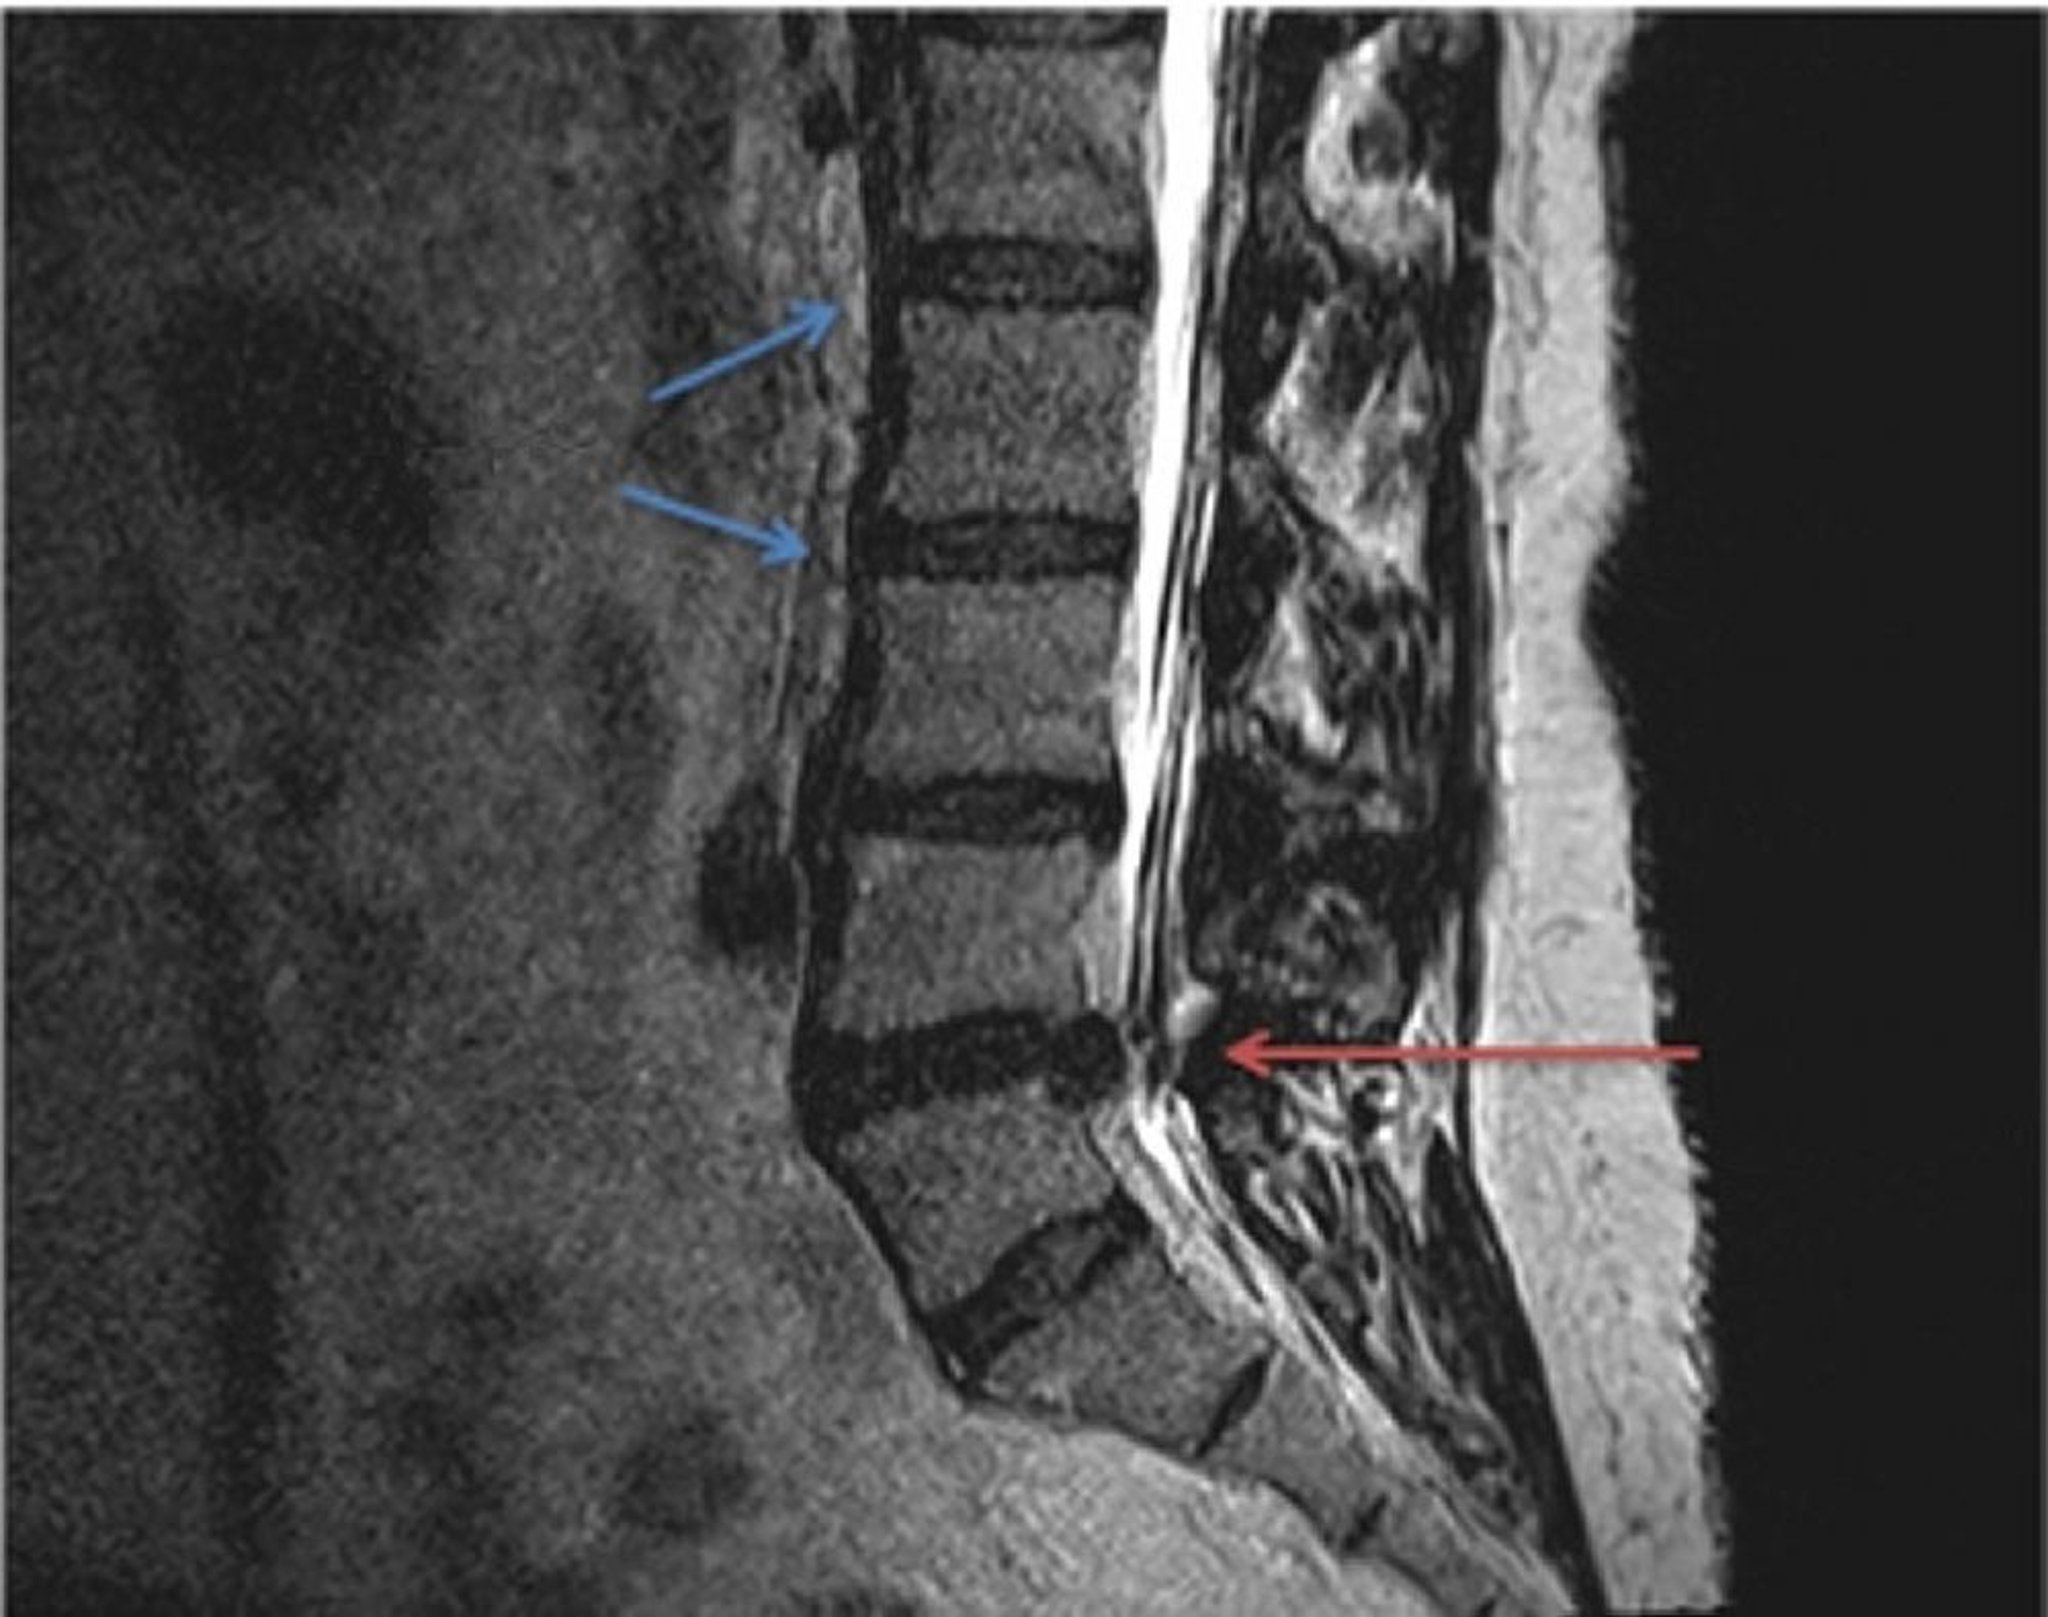

Comparison of normal (blue arrows) and herniated lumbar disc anatomy in a T2-weighted MRI scan. The herniated disc, located between the L4 and L5 vertebrae (red arrow), is pinching the spinal nerve extending from the spinal cord, resulting in localized or radiating pressure and pain.